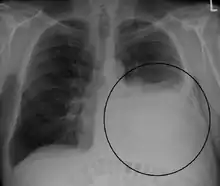

A pleural effusion appears as an area of whiteness on a standard posteroanterior chest X-ray.[7] Normally, the space between the visceral pleura and the parietal pleura cannot be seen. A pleural effusion infiltrates the space between these layers. Because the pleural effusion has a density similar to water, it can be seen on radiographs. Since the effusion has greater density than the rest of the lung, it gravitates towards the lower portions of the pleural cavity. The pleural effusion behaves according to basic fluid dynamics, conforming to the shape of pleural space, which is determined by the lung and chest wall. If the pleural space contains both air and fluid, then an air-fluid level that is horizontal will be present, instead of conforming to the lung space.[8] Chest radiographs in the lateral decubitus position (with the patient lying on the side of the pleural effusion) are more sensitive and can detect as little as 50 mL of fluid. At least 300 mL of fluid must be present before upright chest X-rays can detect a pleural effusion (e.g., blunted costophrenic angles).

Massive left-sided pleural effusion (whiteness) in a patient presenting with lung cancer.